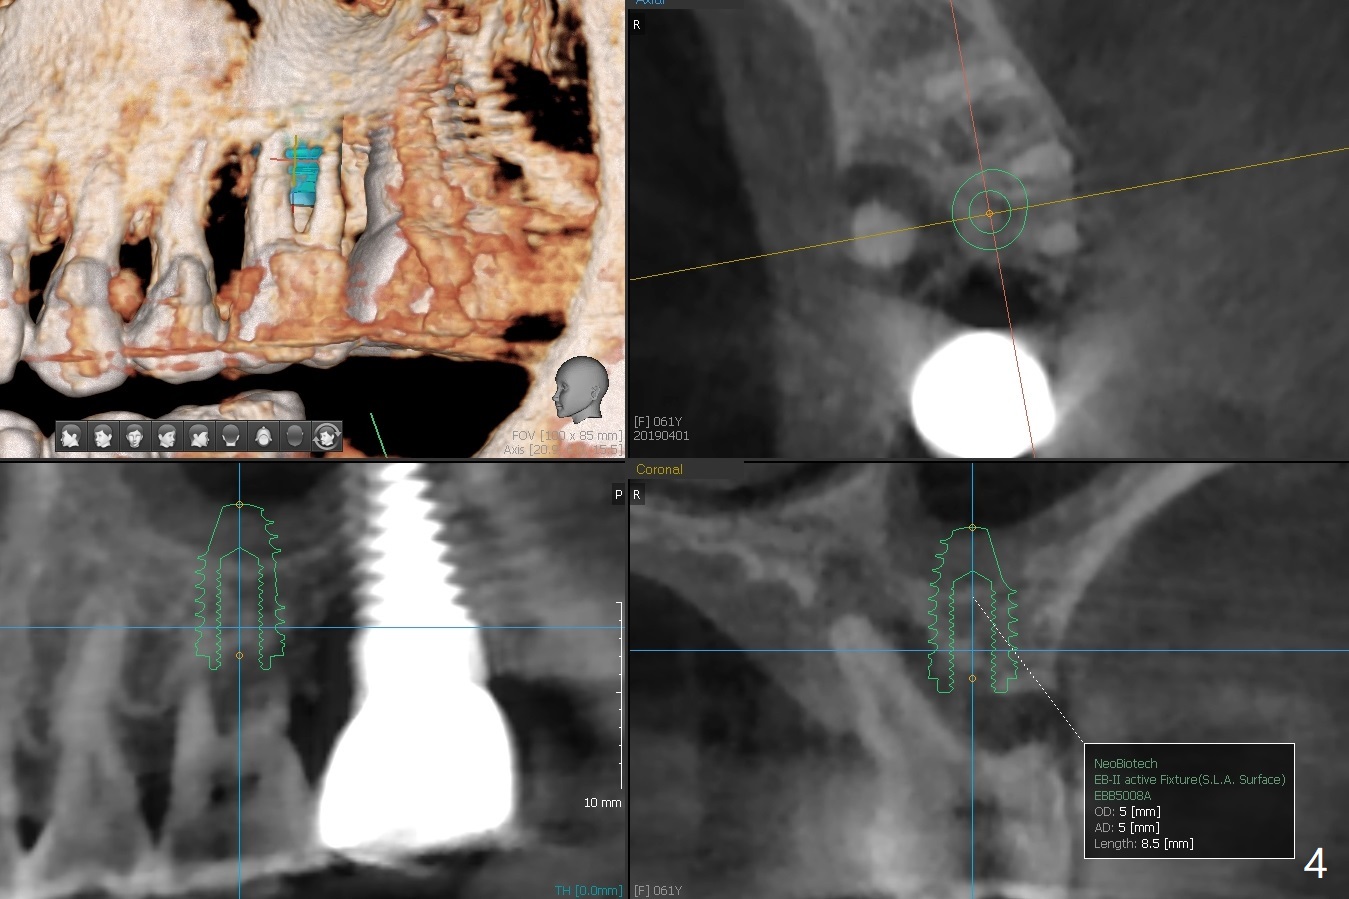

A 61-year-old woman requests implant at #14 because of mobility after exfolia-tion of the tooth #18 (Fig.1). Because of severe bone loss, especially palatal (Fig.2,3 P), osteotomy will be initiated with guide as buccal as possible (Fig.4). To reduce abutment screw loosening, a 5x11 mm tissue-level implant will be placed (Fig.5 blue (pink: abut-ment)).